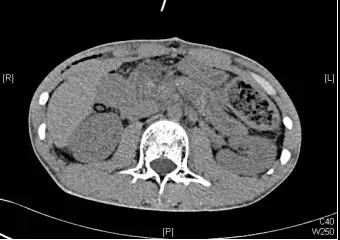

7月25日,严茂林带领团队为小黄施行了“保留十二指肠的全胰头切除、胰尾切除、胰管切开取石、胰肠吻合术”。术中探查显示,小黄胰腺呈慢性胰腺炎改变,与周围组织粘连致密,全胰可扪及多发质硬结石。

情况棘手,医生进行了长达4小时的精雕细琢,进行全胰头的解剖性切除,并完整保留了胰十二指肠上、下血管弓及胆总管。之后医生沿残余胰腺长轴纵行切开主胰管,取净主胰管及分支胰管的结石,切除胰尾约100px,将空肠与纵行切开的主胰管行胰肠吻合。

所幸,历经约7个小时的努力,医生们顺利闯过手术禁区,术中仅出血约100ml。术后,小黄恢复良好,第八天顺利出院,目前进一步随访,他的情况也很良好。

(术后CT图)